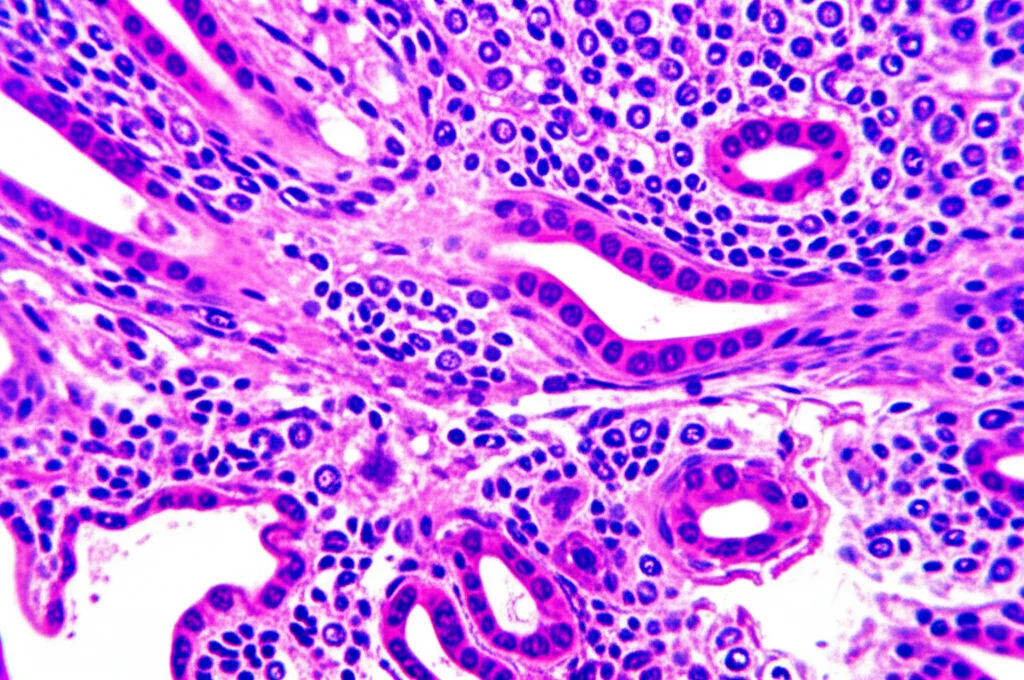

L’Idea: Sfruttare l’Ematossilina-Eosina (HE) con l’IA

Qui entra in gioco la nostra idea un po’ folle, ma affascinante. E se potessimo “leggere” lo stato di HER2 direttamente dai vetrini colorati con Ematossilina ed Eosina (HE)? Questi sono i vetrini standard, quelli che si usano per la prima analisi morfologica di un tessuto. L’ipotesi di partenza è che le differenze a livello molecolare (come l’espressione di HER2) spesso si traducono in cambiamenti visibili nella forma e nella struttura delle cellule (la morfologia, appunto), anche se non sono evidenziate da colorazioni specifiche come l’IHC.